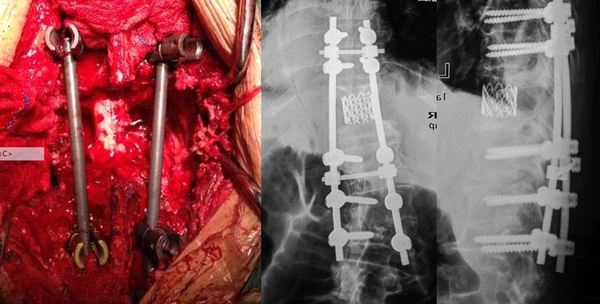

胸椎结核,病灶刮除椎体侧方钉棒系统内固定术! [病例帖]

图片尺寸888x666

外科团队完成侧前方小切口胸椎结核病灶清除,钛网植骨融合内固定手术